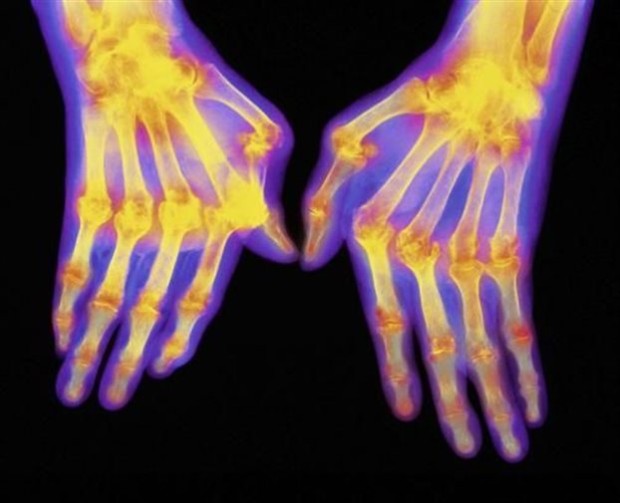

Η νέα γενετική γνώση αναμένεται να οδηγήσει σε αποτελεσματικότερα φάρμακα για τη ρευματοειδή αρθρίτιδα

Εντοπίστηκαν περισσότερες από 40 περιοχές στο DNA που σχετίζονται με τη ρευματοειδή αρθρίτιδα και μπορούν να αποτελέσουν στόχους φαρμάκων

Διεθνής ομάδα ερευνητών εντόπισε περισσότερες από 40 νέες περιοχές στο DNA οι οποίες αυξάνουν τον κίνδυνο για ρευματοειδή αρθρίτιδα. Όπως σημειώνουν οι επιστήμονες με δημοσίευσή τους στην επιθεώρηση «Nature» η συγκεκριμένη γενετική έρευνα είναι η μεγαλύτερη του είδους της – περιελάμβανε σχεδόν 30.000 ασθενείς. Εκτιμάται ότι με βάση τη νέα γενετική γνώση θα αναπτυχθούν καινούργια φάρμακα που θα οδηγήσουν σε καλύτερη αντιμετώπιση της νόσου.